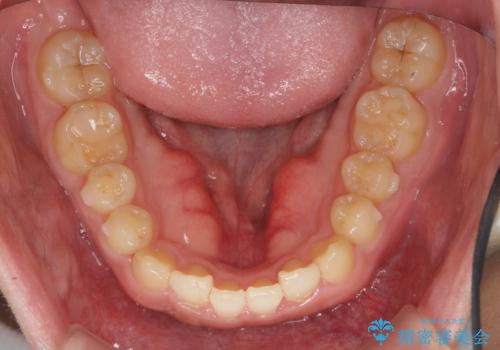

- 前歯の噛み合わせが反対になっていること、前歯の見た目の改善を希望され来院されました。

詳細な矯正検査の結果、顎の歪みが見られたため大きく歯を動かす治療ではなく前歯を主に並べることで前歯の前後関係を改善していきます。

前歯を主に動かす部分矯正であることからマウスピース矯正インビザラインによる治療を計画します。